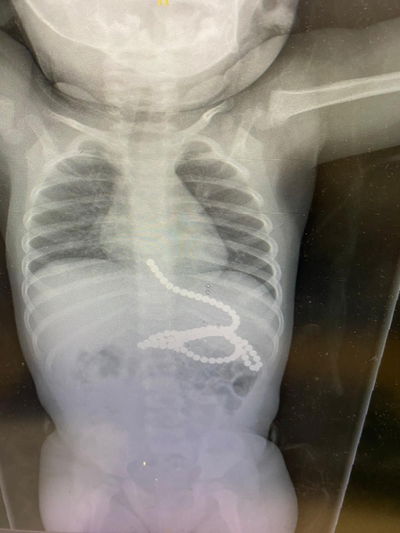

הילד התלונן על כאבי בטן והקיא הרבה, לאחר שהגיע לבית החולים יחד עם הוריו, התברר לאחר סדרת בדיקות מקיפות, כי הילד בלע שמונה מגנטים; "ההורים נקראים להרחיק מגנטים וחלקים קטנים מהישג ידם של ילדים" (חדשות בריאות)

עקב השהות הממושכת של המגנטים במערכת העיכול, והיצמדות חלקים מצינור העיכול האחד לשני ע"י המגנטים, חדרו כמה מגנטים את דופן הקיבה, ולא ניתן היה לשלוף אותם מבלי לסכן את חיי הפעוט. בעקבות זאת הוכנס התינוק לניתוח חירום, לאחר הניתוח הוא הועבר במצב טוב למחלקה (חדשות בריאות)

בן שנתיים בלע מגנטים והובהל לבית החולים, שם הבהירו כי חיין בסכנה, מכיוון שכאשר הפעוט בולע יותר ממגנט אחד, הם נצמדים זה לזה בתוך מערכת העיכול ועלולים לגרום לקרעים במעיים ואז תכולת המזון במעיים נפלטת אל הבטן, לאחר הניתוח, חיי הפעוט ניצלו (חדשות)

למרכז הרפואי מאיר הגיע ילד כבן שמונה ששיחק במגנטים ובלע 20 מהם בעודו משחק אצל חבר • ד"ר זיפמן מסר: "המגנטים נמצאו במעי הגס והוצאו בהצלחה לאחר ניתוח" • הילד נשאר למעקב צמוד לבדיקה שהכל תקין • איך נמנע את המקרה המסוכן הבא? (בריאות, חדשות)

ילד בן 5 שסבל כאבי בטן והקאות, התפנה ל'איכילוב שם הוא הובהל לחדר הניתוח ותחת הרדמה כללית הוצאו מקיבתו ארבעה מגנטים אותם בלע במהלך משחק. תמונות (בריאות)